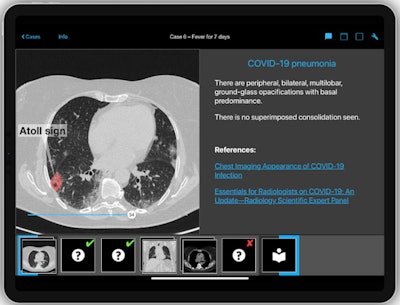

Colored overlays show the radiological signs typical of the relevant pathology in the correction. All images courtesy of Dr. Kay-Geert Hermann.To access the training tool, which takes the form of an interactive case-based quiz, radiologists can download the program for free at berlincaseviewer.de or directly in the Apple App Store. They are then presented with the first of 19 cases, the patient's clinical history and the chance to scroll through the entire CT dataset for that patient, with typically over 50 slices per case.

"A part of the skills to be learnt comprises of picking the slice that best shows the pathology in question, or the relevant radiological signs. The capacity to scroll through all the imaging data of a patient is unique to our tool," noted app founder Dr. Kay-Geert Hermann, consultant radiologist at Charité University Hospital in Berlin. "Another unique feature are the colored overlays showing the radiological signs typical of the relevant pathology once the participant has made a diagnosis."

Participants can move the scroller bar at their own speed through each slice of the chest CT set. They are then asked three questions pertaining to radiological signs visualized, distribution, and a final question about pathology diagnosis. Participants can also access more images in different views after each question, and they can split the screen in two to compare views side by side. Once the participant makes his or her choice about the pathology depicted, the correct answer is provided, along with an annotated image with colored overlays showing the sign that may have been overlooked. Links to scientific papers relevant to the particular case are also provided with the correct answer.